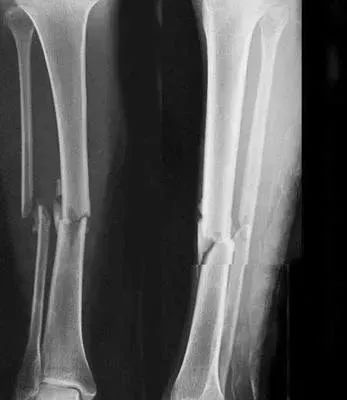

5、小腿踢球时骨折过,还能当兵吗?

四肢单纯性骨折,治愈1年后,X线片显示骨折线消失,复位良好,无功能障碍及后遗症(空降兵除外),合格。